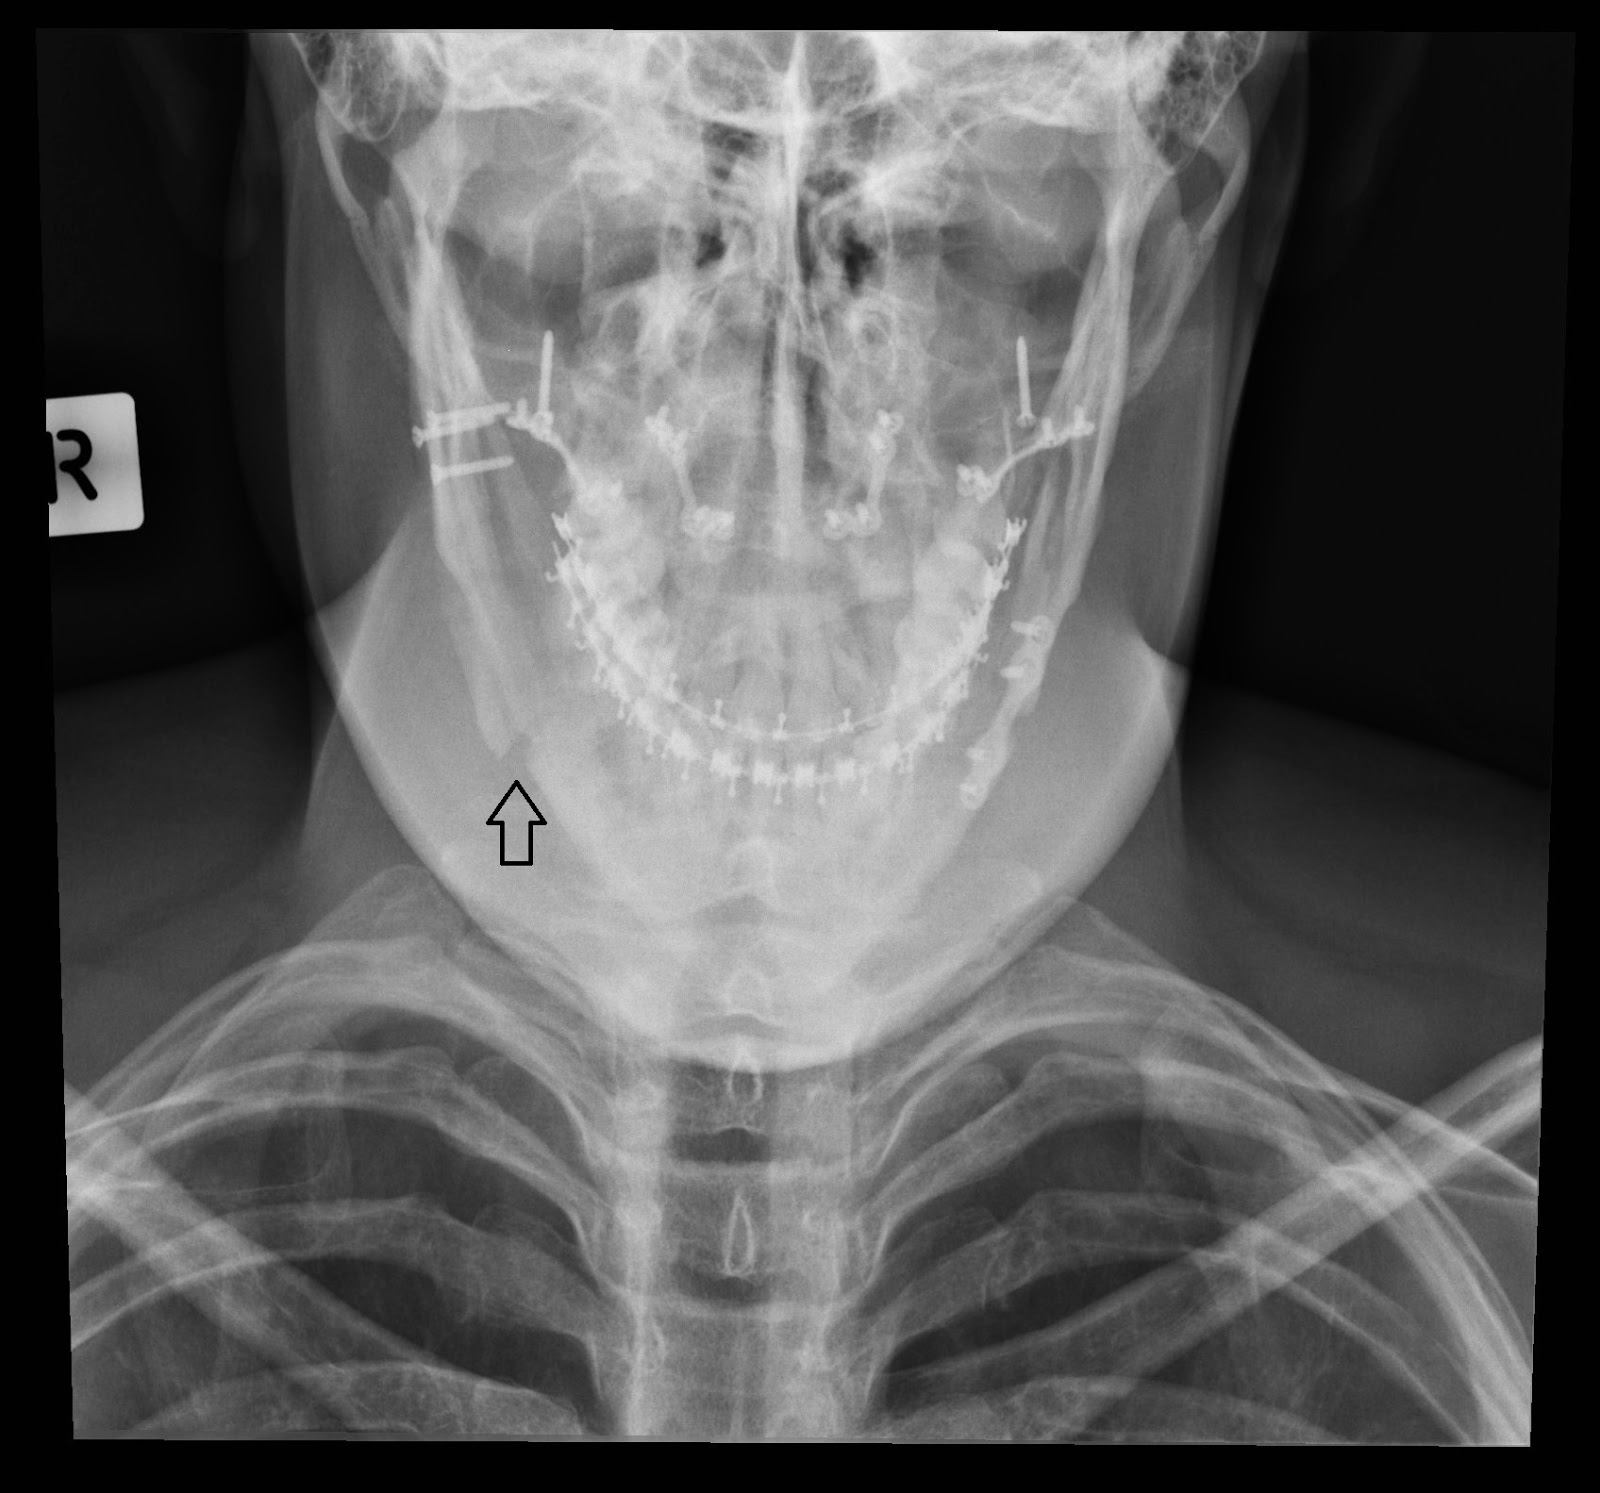

XRays Double Jaw Surgery Double Jaw Surgery X Ray Jaw surgery, or orthognathic surgery, corrects jaw problems and related conditions. jaw surgery, also called orthognathic surgery, is surgery that helps align your upper jaw (maxilla) and lower jaw. what is double jaw surgery? They do a decent job of. double jaw surgery corrects both the upper and lower jaw at the same time. mouth breathing,. Double Jaw Surgery X Ray.

About Orthognathic Surgery Alpharetta GA Double Jaw Surgery X Ray mouth breathing, dry mouth, jaw pain, difficulty chewing, and an inability to bite led me to double jaw surgery. Most people undergo jaw surgery to treat. Jaw surgery, or orthognathic surgery, corrects jaw problems and related conditions. double jaw surgery corrects both the upper and lower jaw at the same time. You can see, quite clearly, the drastic. Double Jaw Surgery X Ray.

What is Jaw Surgery and Why Would I Need It? Doctor Espo Double Jaw Surgery X Ray Jaw surgery, or orthognathic surgery, corrects jaw problems and related conditions. You can see, quite clearly, the drastic change that took place on the operating. mouth breathing, dry mouth, jaw pain, difficulty chewing, and an inability to bite led me to double jaw surgery. Most people undergo jaw surgery to treat. double jaw surgery corrects both the upper. Double Jaw Surgery X Ray.

Before and After Jaw Surgery XRays YouTube Double Jaw Surgery X Ray jaw surgery, also called orthognathic surgery, is surgery that helps align your upper jaw (maxilla) and lower jaw. double jaw surgery corrects both the upper and lower jaw at the same time. Learn more about how this surgery works and how we can help. They do a decent job of. Jaw surgery, or orthognathic surgery, corrects jaw problems. Double Jaw Surgery X Ray.

XRay of total TMJ replacement and upper jaw surgery. jawsurgery Double Jaw Surgery X Ray Learn more about how this surgery works and how we can help. what is double jaw surgery? Most people undergo jaw surgery to treat. jaw surgery, also called orthognathic surgery, is surgery that helps align your upper jaw (maxilla) and lower jaw. You can see, quite clearly, the drastic change that took place on the operating. Jaw surgery,. Double Jaw Surgery X Ray.